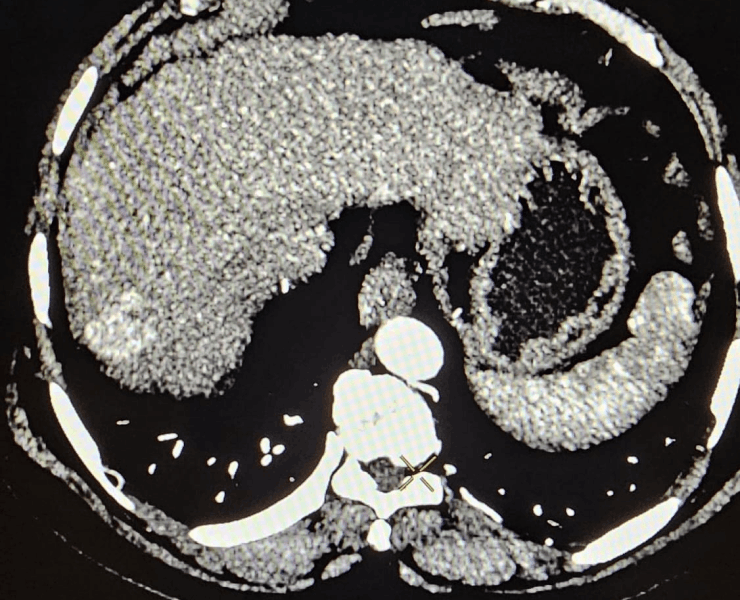

Liver Cancer Treatment

Many liver cancer patients are not suitable for surgery because of tumour location, multiple lesions, underlying liver disease or general health. In such cases, interventional radiological procedures can offer effective, targeted options:

- Thermal ablation (radiofrequency or microwave): destroys tumour tissue by heating it from within through a thin needle placed under USG/CT guidance.

- Chemoembolization (TACE): delivers chemotherapy directly into the tumour’s blood supply, followed by embolic particles to block the vessels and cut off nutrition to the cancer.